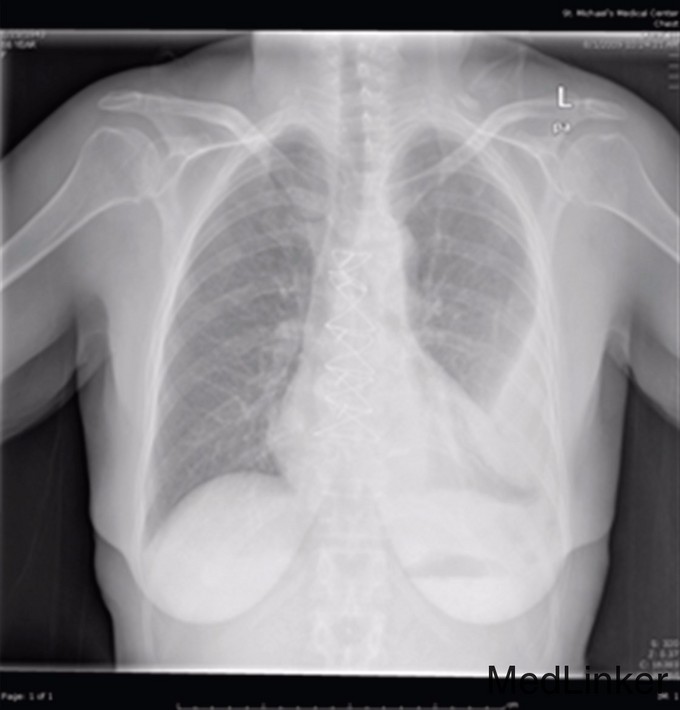

查体:左肺底部闻及浊音,呼吸音降低,未闻及干湿啰音。下肢有水肿, 无杵状指,未查见特殊。血常规提示血象高,白细胞11800/mm3,中性粒细胞占84%,淋巴细胞占9%。胸部X线显示左胸下三分之二混浊(图1),胸部CT提示左侧胸部大面积包裹性积液(图2),胸水生化常规提示乳酸脱氢酶292U/L,总蛋白4.0 g/dL,白细胞1033/mm3,革兰染色球杆菌阳性。根据light标准判断胸水为渗出液。